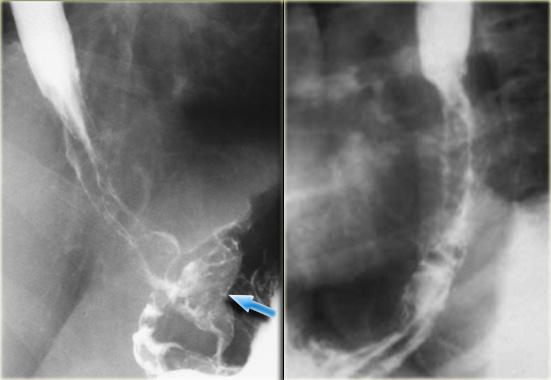

Bên trái là hình ảnh giãn tĩnh mạch thực quản hướng xuống (Downhill varices) ở bệnh nhân tắc nghẽn tĩnh mạch chủ trên do bệnh histoplasmosis.

Trên phim chụp thực quản cản quang, các khuyết đọng thuốc không hằng định (mũi tên) biểu hiện giãn tĩnh mạch hướng xuống ở thực quản trên.

Hình chụp mạch máu cho thấy các mạch máu bàng hệ bao gồm tĩnh mạch liên sườn trên trái giãn rộng (mũi tên).

Phim chụp thực quản cản quang cho thấy các khuyết đọng thuốc không hằng định (mũi tên xanh dương) do giãn tĩnh mạch hướng xuống ở thực quản trên.

CT cho thấy giãn tĩnh mạch thực quản (mũi tên đỏ) và trung thất.

Tiếp tục xem hình chụp tĩnh mạch.

Hình chụp tĩnh mạch chi trên cho thấy tắc nghẽn tĩnh mạch chủ trên (SVC).